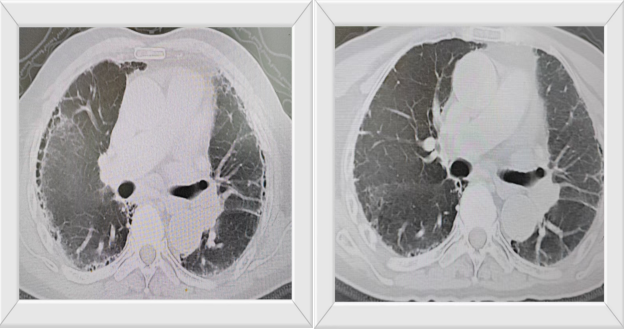

患者在住院过程中(2024-12-27)出现咳嗽,活动后心累、气促,遂完善相关辅助检查:B型脑钠肽(BNP):207.33 pg/ml,尿常规:*蛋白质 +1   0.3 g/l、微白蛋白 >=100 mg/L。胸部CT示:1、慢性支气管炎、肺气肿征,伴间质性肺炎,请结合临床及治疗后复查。2、双肺多叶段支气管轻度扩张。3、双侧胸膜增厚、粘连。4、心脏体积增大,主动脉及冠状动脉钙化,心包少量积液。肝肾功、血常规、电解质等正常。

患者间质性肺炎合并肾损害,但需明确病因,考虑系统性疾病可能性较大,遂完善血沉 108.80 mm/h,后经过科室医疗团队积极讨论后,完善血管炎五项:抗中性粒细胞胞浆抗体-PANCA 阳性、抗心磷脂(ACA)抗体定量 160.90 RU/ml、抗髓过氧化物酶抗体(MPO-Ab) 阳性。据检查结果,并完善相关检查排除其他后,临床诊断(2025-01-10):ANCA相关性血管炎(显微镜下多血管炎)。患者高龄,后续治疗副反应极大,科室再次经过积极讨论,一致认为患者虽年龄极大,但平素身体素质好,予以尼达尼布抗纤维化,醋酸泼尼松以及口服中药汤剂等治疗。

治疗前后部分有意义检查对比: